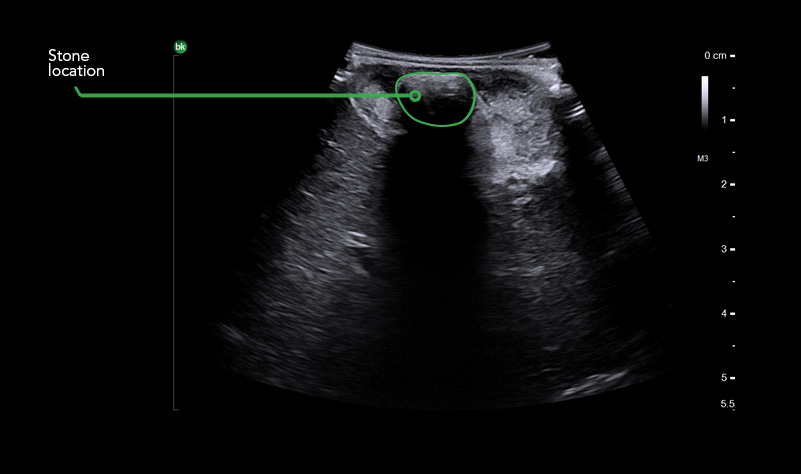

Gallstone

CHOLEDOCHOLITHIASIS DETECTION

iUS helps differentiate between sludge, stone, polyps, cysts, and tumors when determining if there is a presence of gallstones in the common bile duct.5.6

When helping to detect choledocholithiasis, iUS resulted in a 90-96% sensitivity rate and 100% specificity rate.7